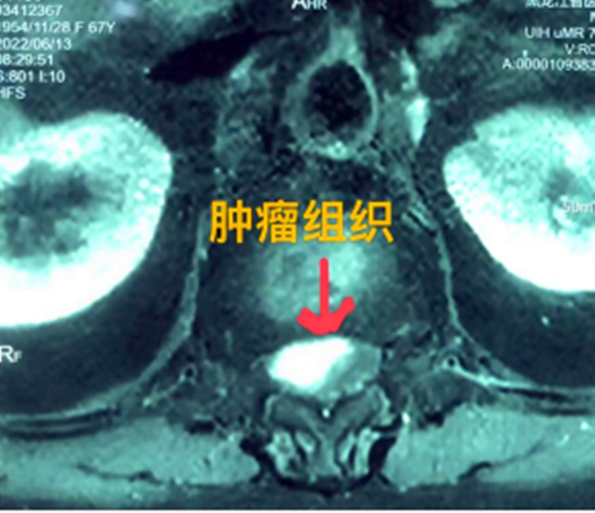

據(jù)省醫(yī)院神經(jīng)外一科陶宇醫(yī)生介紹,家住外地的張大娘最近總感覺雙下肢疼痛、無力,且排尿困難及便秘,伴有行走困難。時間長了,張大娘病情逐漸加重,劇烈的疼痛甚至讓她無法完整入睡。在當(dāng)?shù)蒯t(yī)院,張大娘按腰椎肩盤突出接受治療,但未見好轉(zhuǎn),隨后進(jìn)行的胸椎MRI(核磁共振)檢查,結(jié)果不禁讓張大娘和家屬瞠目結(jié)舌,原來張大娘患的竟然是少見的脊髓腫瘤。

張大娘住進(jìn)了黑龍江省醫(yī)院神經(jīng)外一科,該科孫國章主任醫(yī)師熱情地接待了張大娘,并邀請骨外一科專家共同為她進(jìn)行了聯(lián)合會診。發(fā)現(xiàn)張大娘病情十分復(fù)雜棘手,脊髓腫瘤體積較大,充滿髓腔且神經(jīng)已經(jīng)完全受壓,需要手術(shù)來完整切除。同時還發(fā)現(xiàn)張大娘的胸腰部曾受過兩次外傷,伴有多處骨折,這對接下來的手術(shù)操作帶來一定影響。